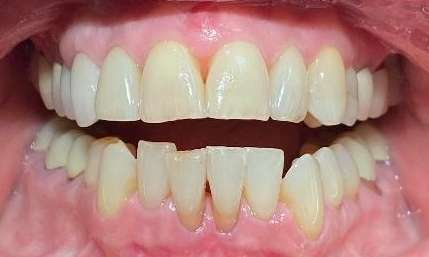

When this patient came into our office, she told us she had orthodontics as a teen and her open bite was the best they could do. She complained that she couldn't bite into a sandwich without the lettuce pulling out through her teeth since she couldn't get her front teeth to touch! In less than a year, Dr. Farahani corrected the remaining open bite and gave her the ability to eat all foods! What a life changer!